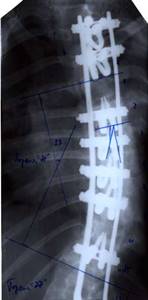

До сих пор в ортопедии принято множество методик измерения угла искривления позвоночника, и, соответственно, множество различных классификаций с разными величинами углов в градусах. Измеряется искривление так: на рентгенограмме надо провести несколько прямых линий между позвонками, а затем измерить углы между ними. В нашей стране наиболее распространена классификация, предложенная В.Д. Чаклиным. В иностранных научных источниках чаще приводится метод Дж. Кобба. Суть его заключается в следующем: на рентгеновском снимке позвоночника врач измеряет S-образное двойное искривление. В верхнем участке искривления с помощью линейки проводят две горизонтальные линии: одна над верхним позвонком, от которого идет кривизна, другая - над нижним. Если провести еще две линии, идущие перпендикулярно первым, образуется угол. Его и измеряют в градусах

Классификация выраженности сколиоза по В.Д. Чаклину (слева), по Лж. Коббу (справа) Степени тяжести сколиоза (углы искривления позвоночника, в градусах) Графический расчет на рентгенограмме: а - I степень; б - II степень; в - III степень; г - IV степень.

| По В.Д. Чаклину | По Дж. Коббу |

| I степень 180 - 175 | меньше 15 |

| II степень 175-155 | 20-40 |

| III степень 155-100 | 40-60 |

| IV степень меньше 100 | больше 60 |